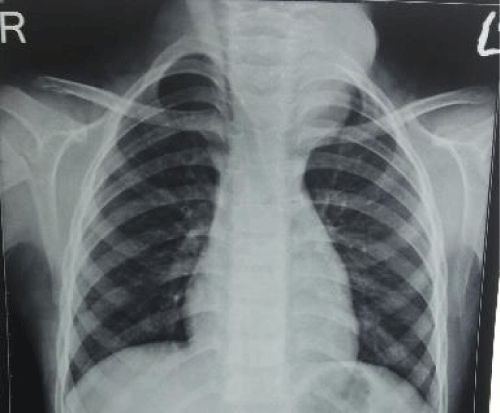

On examination, the mass was 10cm X 5cmX 5cm, normal temperature, non-tender, lobulated, firm, fixed to underlying structure, but free overlying normal skin, extending from chin to clavicle involving left anterior triangle of the neck, displacing trachea to the right and left common carotid anteriorly (Figure 1). Finger could not be passed between the lower end of mass and suprasternal notch, suggesting anterosuperior mediastinal extension. There was no other palpable mass or cervical lymph node. Oral cavity examination was within normal limits.

Figure 1:

The Chest X- ray PA view confirmed tracheal deviation to right (Figure 2). Fine needle aspiration cytology revealed fragments of mature adipose tissue and fibrous tissue in background with no nuclear atypia. Ultrasonography Neck revealed lobulated soft tissue mass and Doppler ruled out hypervascularity as is usually seen in malignant mass.

Figure 2: